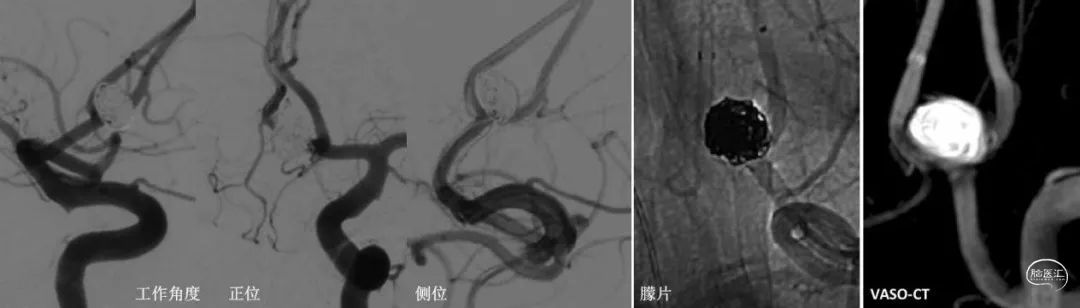

图片8:术后工作角度、标准正侧位造影及VASO扫描显示动脉瘤栓塞满意,瘤体瘤颈未见造影剂染色,RaymondⅠ级。